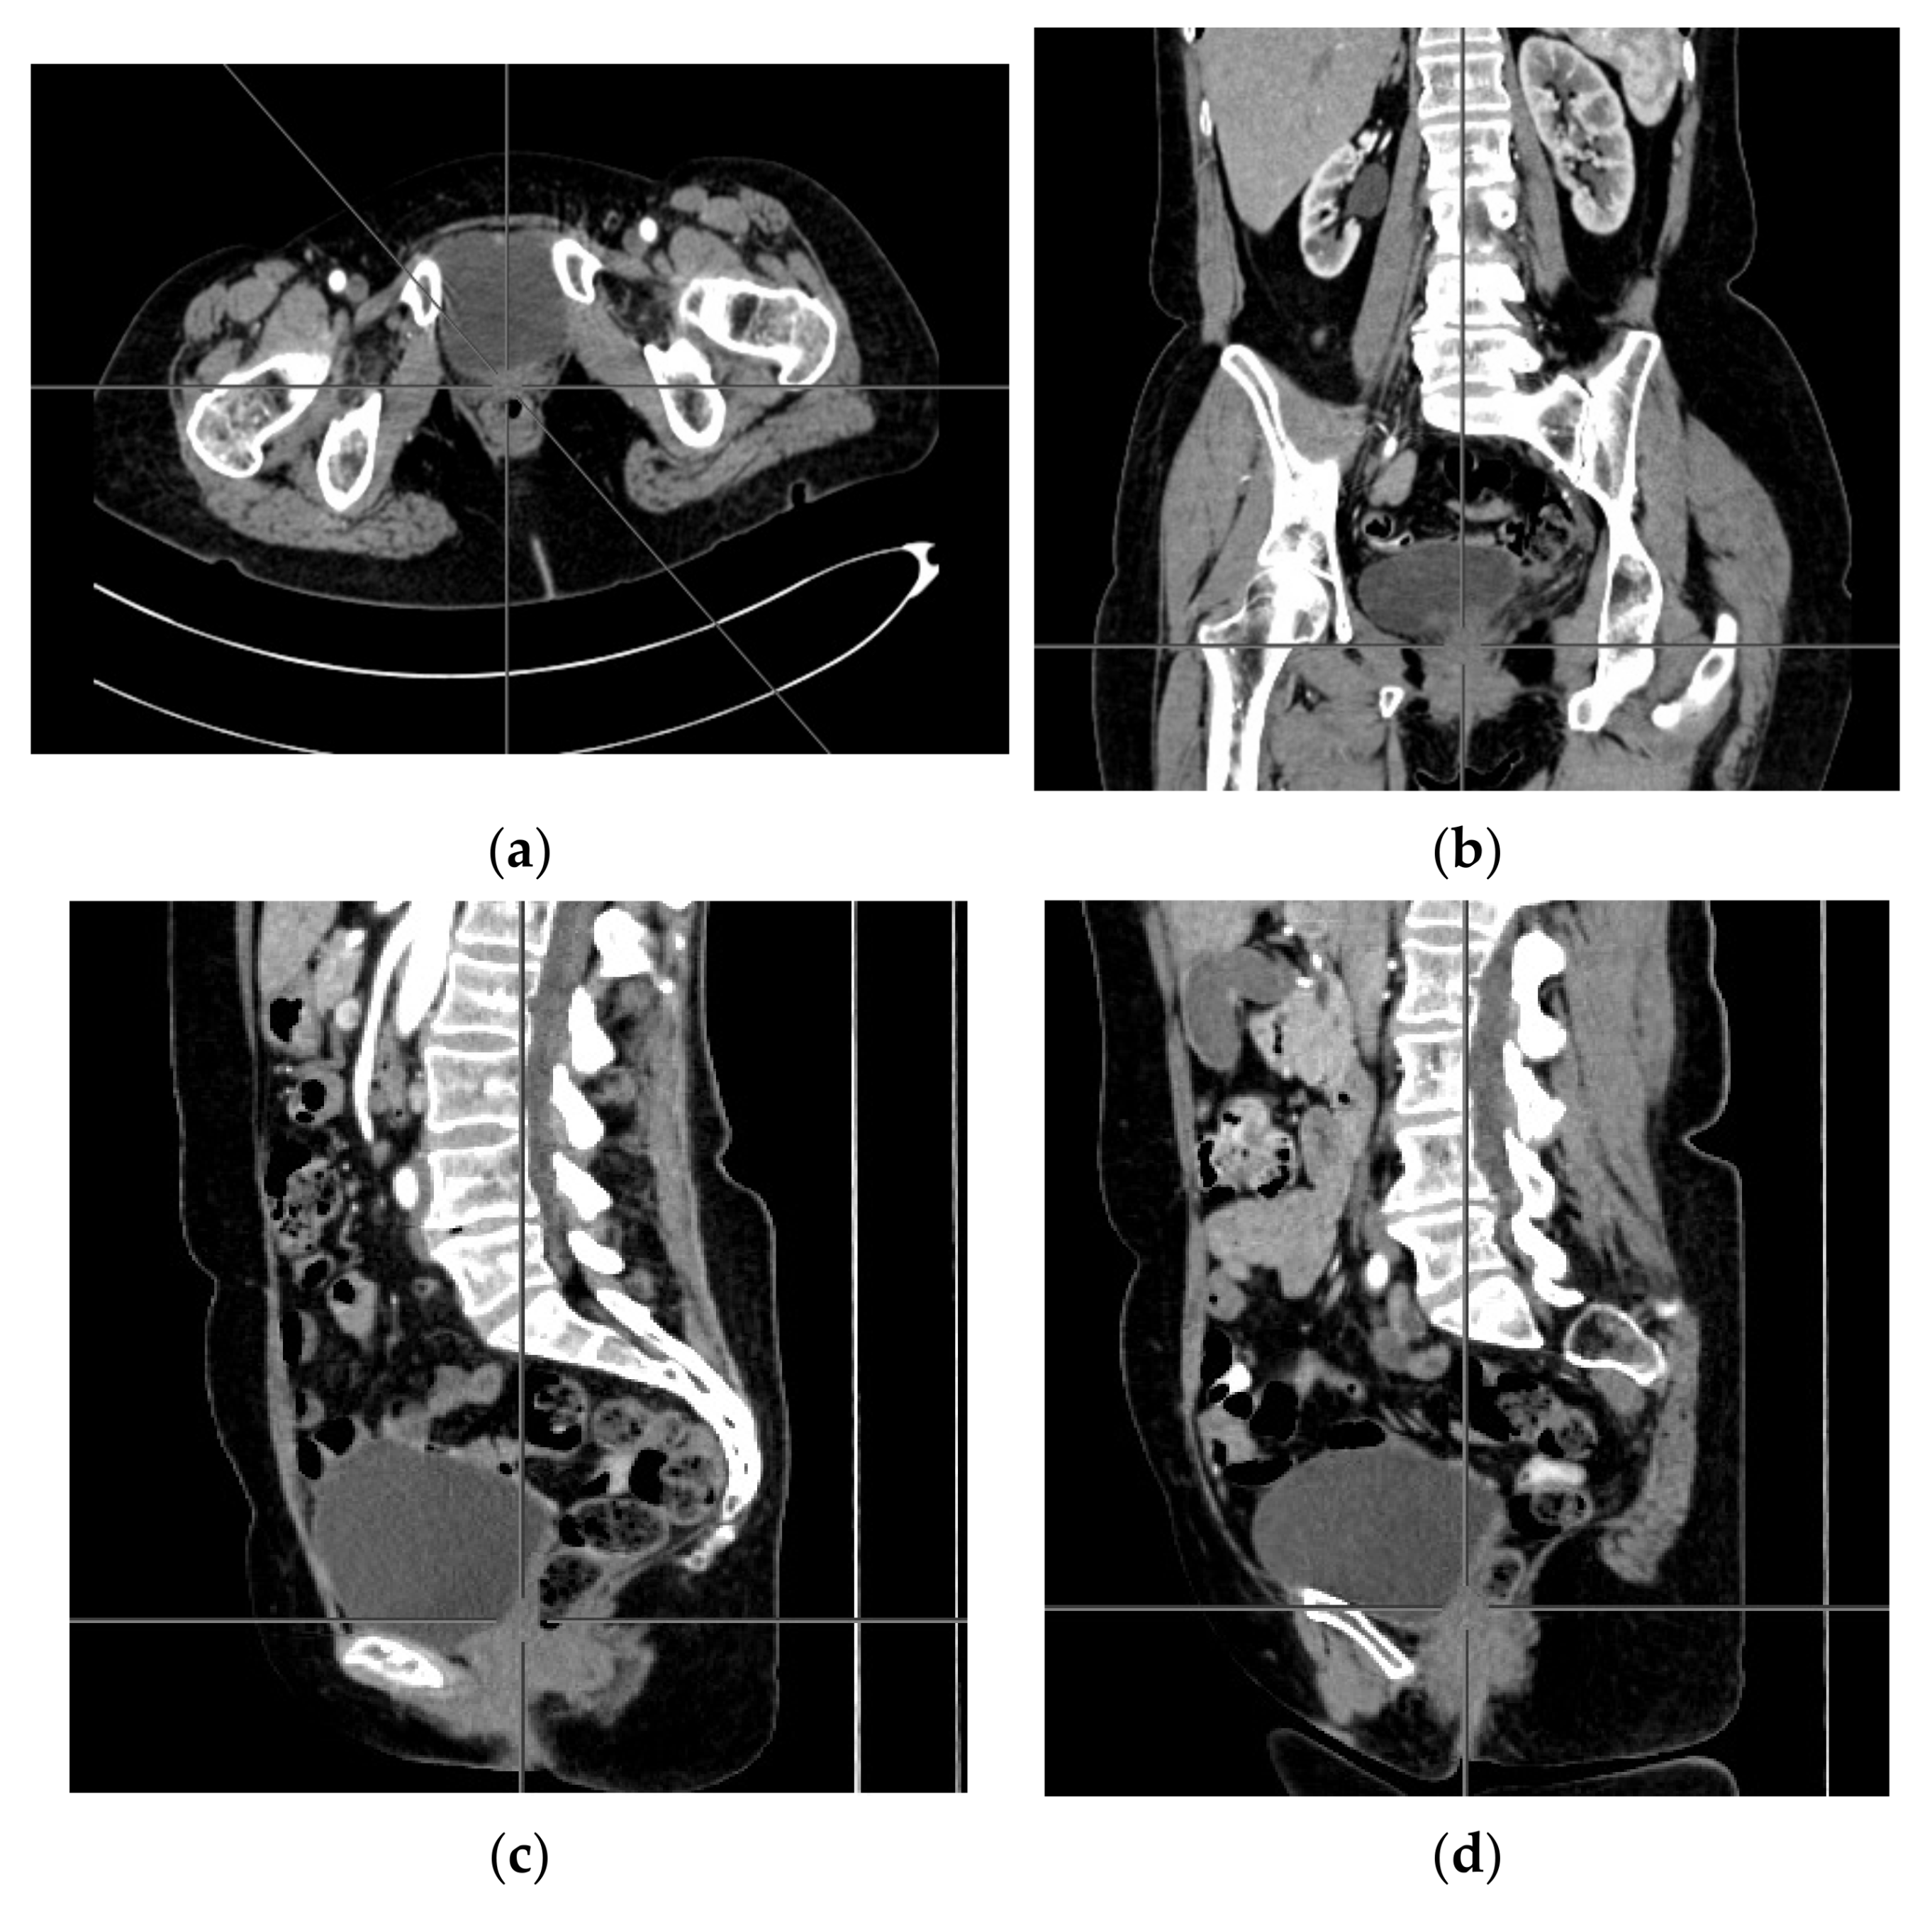

A computer tomography of the abdomen and pelvis was also performed every 3 months for the possible detection of ovarian cancer recurrence. No CT changes suggestive of recurrence were observed in the patient during the treatment. There are illustrates scans on the same section from CT performed at the beginning of PARP inhibitor treatment (Figure 2) and before 48 cycle of olaparib chemotherapy (Figure 3).

Figure 3.

(a–d) CT scans performed before 48 cycle of olaparib treatment.